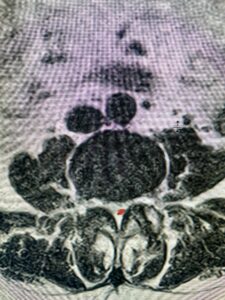

This 54-year-old morbidly obese female presents with progressive back and leg pain and quadriceps weakness. She had no diabetes. She failed all means of conservative management including physical therapy and epidural injections. On imaging she had severe stenosis at L3-4 with a disc protrusion and a slight grade 1 spondylolisthesis at L3-4 (Fig 1). We performed dynamic lumbar x-rays which demonstrated instability at L3-4 and L4-5 (Fig 2). The patient wished to have surgery. We performed an L2-4 decompressive laminectomy and L3-5 in situ fusion because of her instability. Post operatively the patient had relief of leg pain, although the patient was slow to mobilize.

Fig 1b: Axial lumbar T2-weighted MRI demonstrating severe lumbar stenosis (red dot)